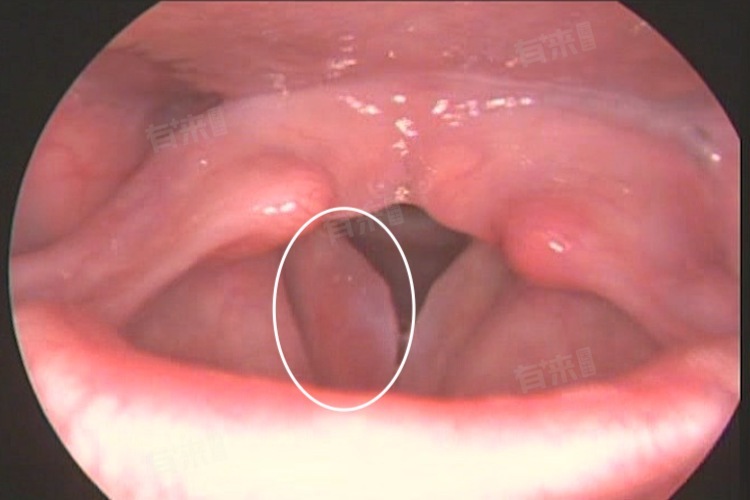

- 如果声带水肿伴有严重损伤,如声带小结、息肉等,上述病变通常需要专业医疗手段进行干预和治疗,才能消除水肿并恢复声带正常功能,也无法自己消退。